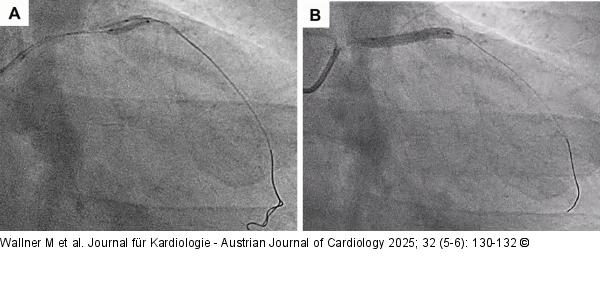

Abbildung 4A-B: Buddy ballon technique Buddy ballon technique: 2 wires (Turntrac™) advanced into the LAD. 1.5 (1 dot in the centre) and 2.5 mm (two dots at the edges) NC-balloons placed in parallel in the heavy calcified proximal LAD and inflated simultaneously with high pressure (A). Stent deployment (DES; 4.0 x 28 mm) (B) |

Abbildung 4A-B: Buddy ballon technique

Buddy ballon technique: 2 wires (Turntrac™) advanced into the LAD. 1.5 (1 dot in the centre) and 2.5 mm (two dots at the edges) NC-balloons placed in parallel in the heavy calcified proximal LAD and inflated simultaneously with high pressure (A). Stent deployment (DES; 4.0 x 28 mm) (B) |